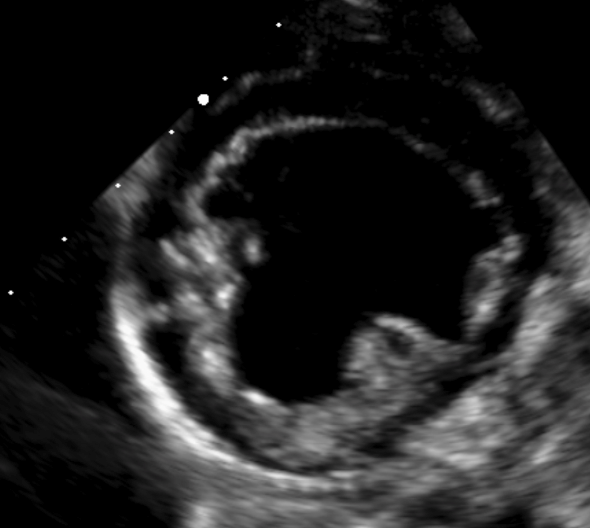

• Étude de cas interactifs à partir d’images fixes et de vidéos en échographie cardiaque (modes 2D, TM, Doppler).

• Principes de l’échocardiographie 2D, TM et Doppler appliqués aux cardiopathies acquises.